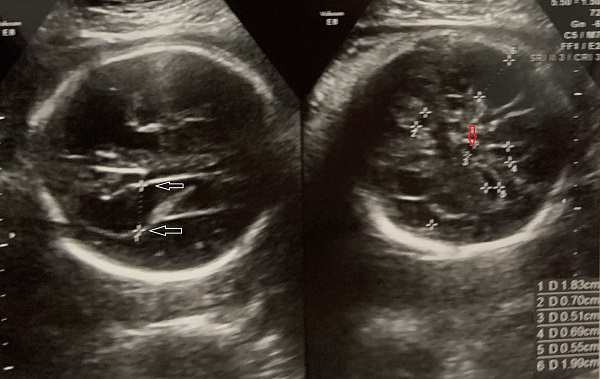

Cuerpo calloso: es una estructura compuesta por haces nerviosos cuya función es la de conectar e integrar regiones corticales homólogas entre ambos hemisferios cerebrales. Su ausencia total puede conducir a problemas cognitivos y del desorrollo psicomotriz o pasar totalmente desapercibida. Su ausencia parcial, paradójicamente, se asocia con peor pronóstico. Como estructura ecográfica, es una de las más bellas que hay en el cerebro pero, para obtenerla se requiere pericia y muy buena resolución ecográfica. Sus alteraciones congénitas son diagnóstico de problemas primarios del desarrollo cerebral y se manifiestan con cambios indirectos en otras secciones cerebrales, especialmente ventriculomegalia.

Lesiones cerebrales

En este resúmen gráfico se incluye la mayor parte de las lesiones cerebrales congénitas visibles en vida fetal; los cortes transversales expuestos aquí son insuficientes para algunas de ellas y los hallazgos pueden modificarse en el tiempo, usualmente manifestando mayor número de elementos anómalos. Muy pocas condiciones mejoran con el tiempo